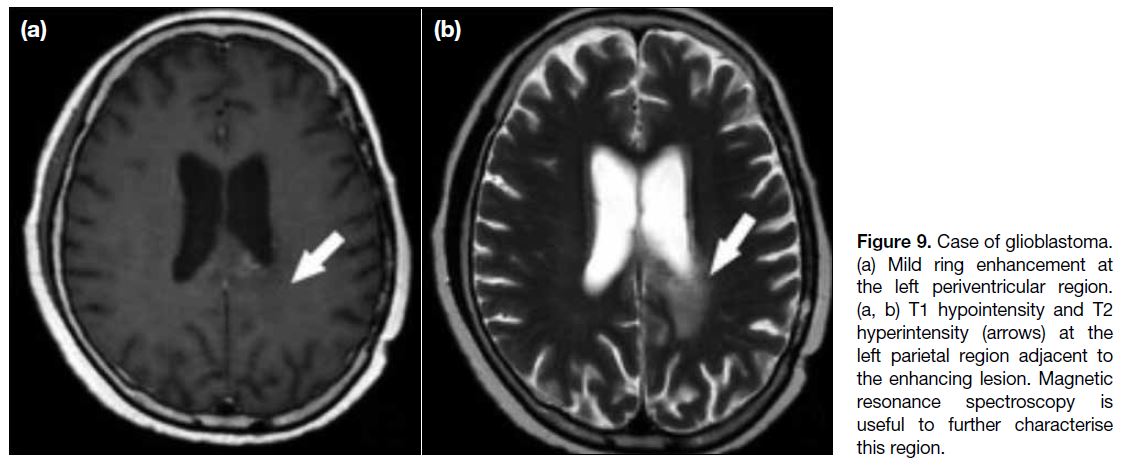

those regions (Figures 9 and 10).[16]

Figure 9. Case of glioblastoma.

(a) Mild ring enhancement at the left periventricular region. (a, b) T1 hypointensity and T2 hyperintensity (arrows) at the left parietal region adjacent to the enhancing lesion. Magnetic resonance spectroscopy is useful to further characterise this region.